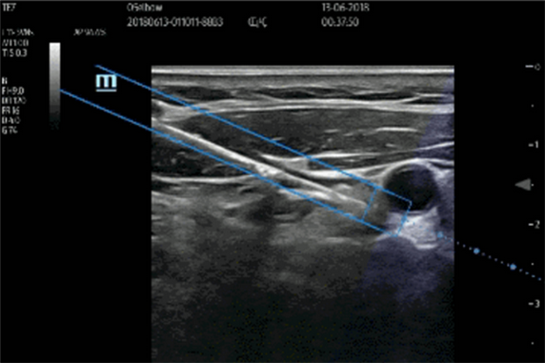

平面外穿刺时,显示针体投影并预测交点

对此,西安市红会医院特地引进了迈瑞公司自主研发的基于磁场感应的4D穿刺针引导espacial Navi磁影技术。穿刺针引导磁影技术能在穿刺过程中显示针体在超声平面的投影,通过投影的位置引导针体到超声平面的行进路线,并且预测穿刺目标位置。这样大大降低了麻醉医生的穿刺难度也提高了穿刺成功的概率。